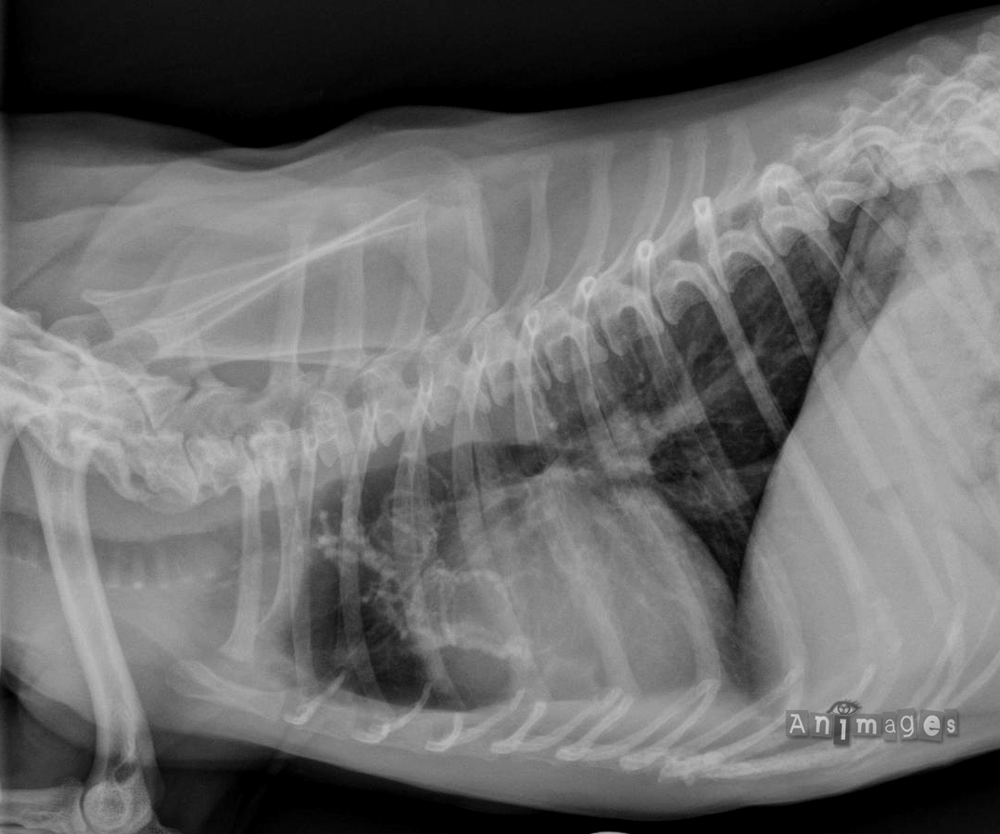

Thorax; latérale